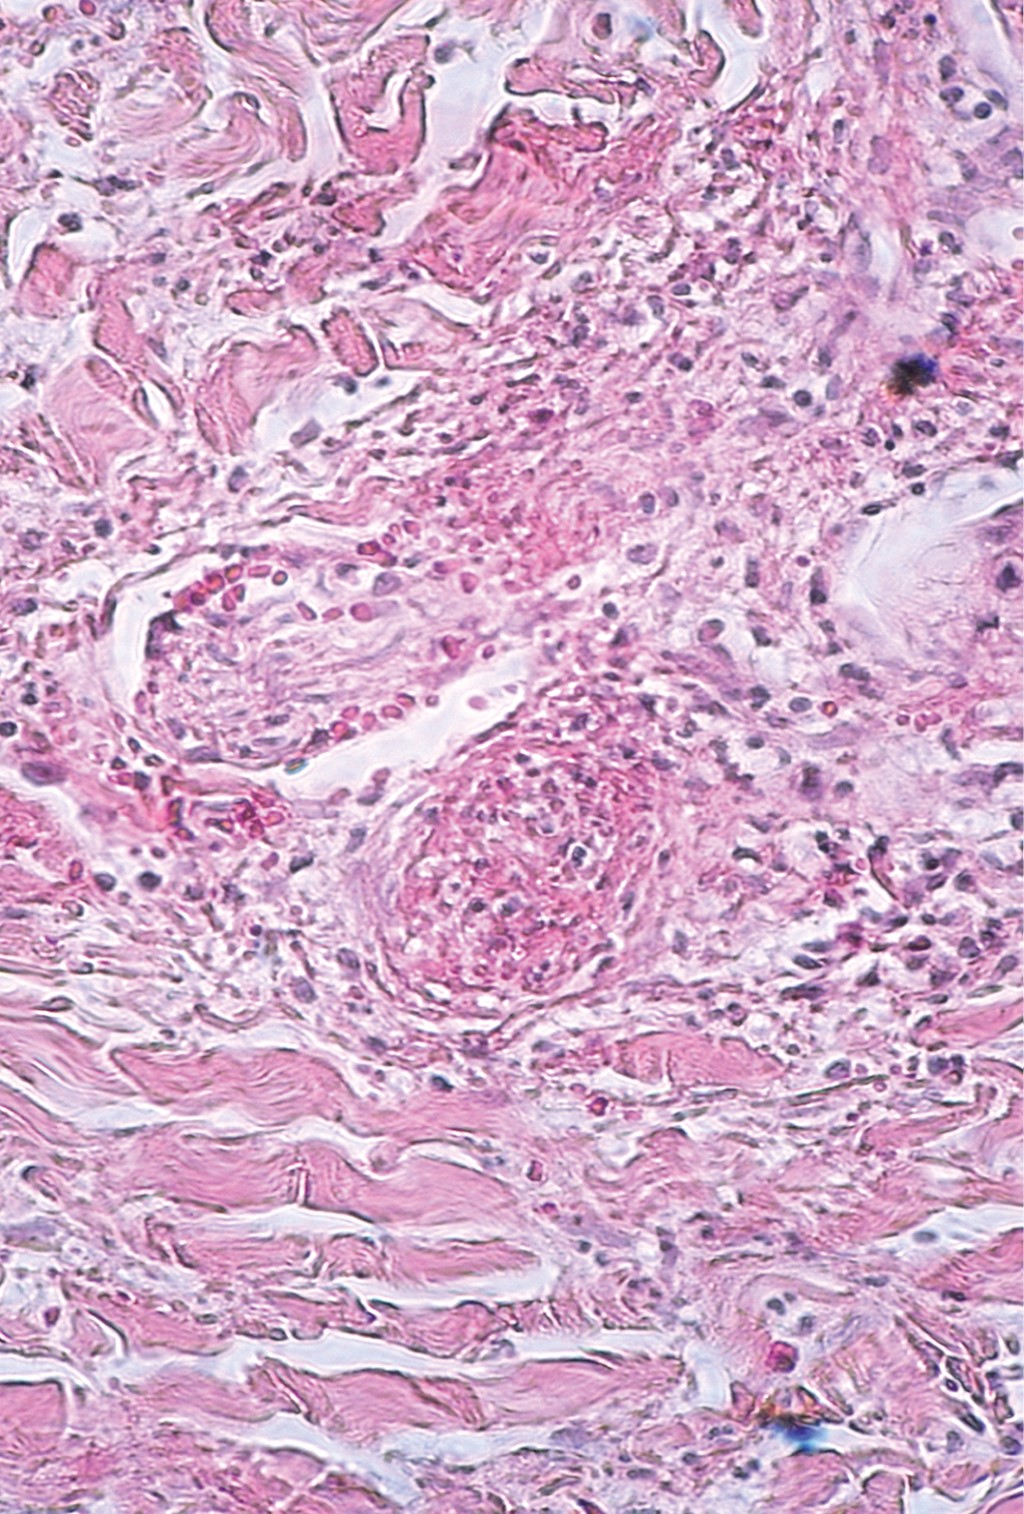

Cutaneous polyarteritis nodosa: presentation of two cases and literature review

Cutaneous polyarteritis nodosa is a form of vasculitis that affects small to medium sized arteries, with unknown incidence due to a low frequency. The exact etiopathogenesis is unknown. Clinically, it is characterized by painful subcutaneous nodules associated to livedo reticularis, that frequently evolves to ulcers on lower extremities, with a chronic and relapsing clinical course. Generally, it only involves skin, however, extracutaneous manifestation has been reported. In this article we describe different clinical presentation and management of two patients with different gender and age.

Figure 3